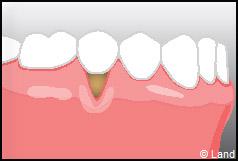

Outre la maladie parodontale, nous pouvons rencontrer des défauts de la gencive qui n’ont pas une origine infectieuse. Les plus fréquents de ces défauts sont les récessions gingivales, qui se traduisent par la migration de la gencive en direction de la racine (la racine est alors à nu).

Les conséquences de cette mise à nu de la racine dentaire sont multiples, le patient peut présenter une hypersensibilité dentaire et l’aspect de ces récessions peut être inesthétique. Dans ce cas, la chirurgie muco-gingivale est recommandée et elle peut se faire de différentes façons.